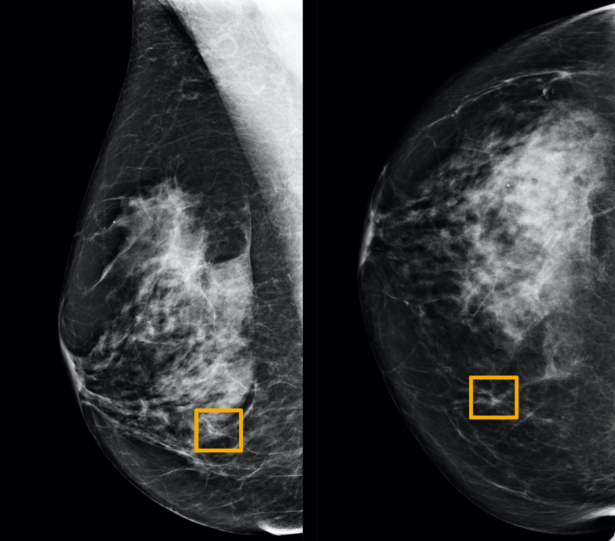

CHICAGO—A Google artificial intelligence system proved as good as expert radiologists at detecting which women had breast cancer based on screening mammograms and showed promise at reducing errors, researchers in the United States and Britain reported.

The study showed the AI system could identify cancers with a similar degree of accuracy to expert radiologists while reducing the number of false-positive results by 5.7 percent in the United States-based group and by 1.2 percent in the British-based group.

It also cut the number of false negatives, where tests are wrongly classified as normal, by 9.4 percent in the United States group, and by 2.7 percent in the British group.